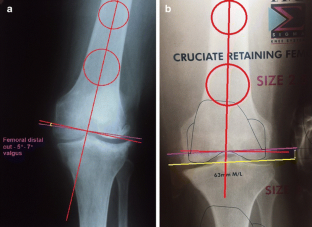

Fig. 1